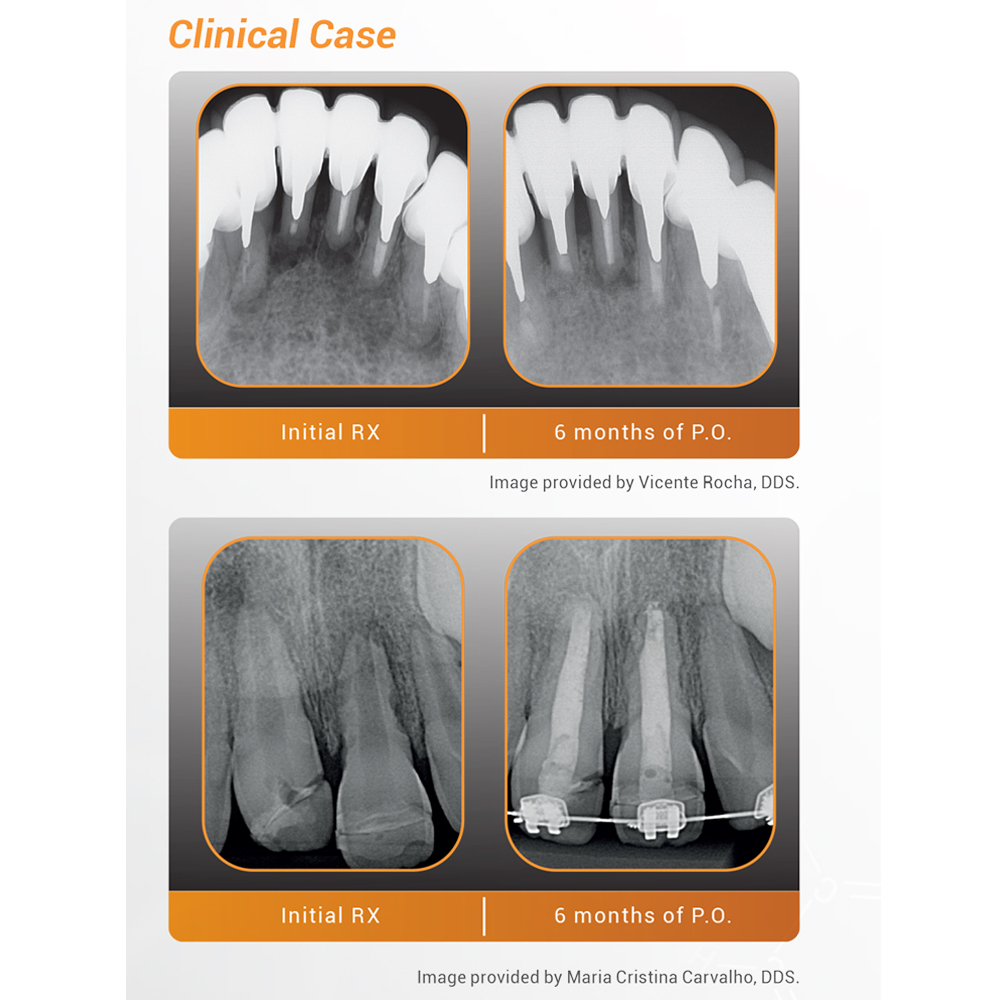

BIO C Repair (0.5gm)

Code: MAT19-131

AU$55.00 (Incl. GST 10%)